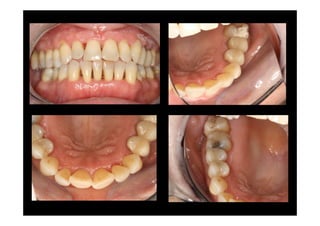

MODIFED WIDMAN FLAP

MODIFIED WF

1 év POSTOP.

(MWF)

Baseline

Baseline X-ray

Periodontal charting